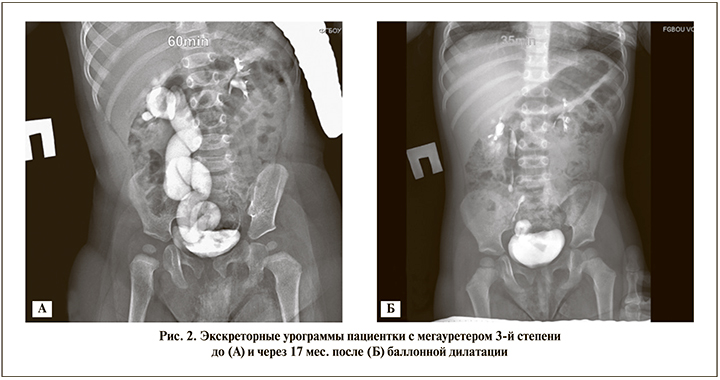

Контрольное обследование позволило определить эффективность баллонной дилатации и активность мочевой инфекции в послеоперационном периоде. Хорошие результаты в виде нормализации пассажа мочи, отчетливой констрикции верхних мочевыводящих путей после однократного лечения диагностированы у 63 (79,74%) пациентов (рис. 2А, Б).

В 16 (20,25%) случаях уретерогидронефроз сохранялся без динамики, этим пациентам в дальнейшем выполнены хирургические вмешательства.